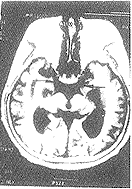

1.2 方法 采用Siemens1.0T和GESignHorizon1.5T超导型MR扫描机,标准头部表面线圈。常规横轴位扫描,用自旋回波序列,T1TR/TE=500/14ms或500/11ms,T2TR/TE=2000/15,层厚8mm,层间距5mm12层,矩阵256×256。在横轴位T1加权图像上取上池层面测量颞叶钩回间距(图1、图2)和经大脑脚层面测量大脑左右径,并计算颞叶钩回间距/大脑左右径比值。

图2 AD患者(右图)

颞叶钩回间距增宽(黑箭头)